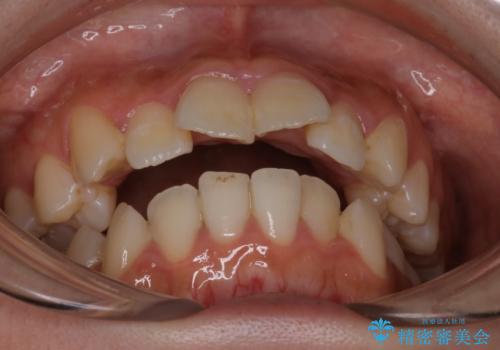

【インビザライン】マウスピースで開咬改善

- 開咬を主訴に来院されました。

IPR(歯と歯の間を削る処置)と顎間ゴムを行いながら、インビザラインで開咬を治療する計画を立てました。

治療をしながら、MFT(口腔筋機能療法)も行っていくことにしました。

歯の移動量が多いケースでしたが、患者様にマウスピースの使用とゴム掛けを頑張っていただいたので

リファイメント1回のみで治療を終わることができました。